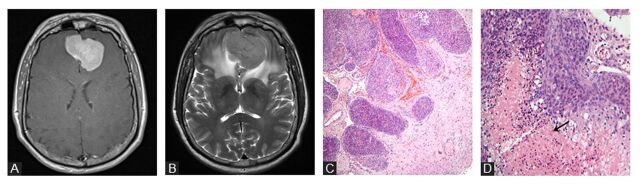

Abstract Image